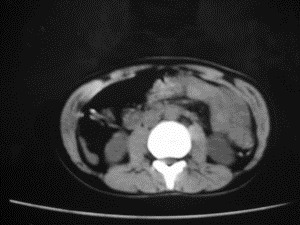

患者女,20岁,被车撞伤3小时,pe:全腹肌紧张,压痛反跳痛,以右上腹为著,肠鸣音减弱。有手术结果。![]() ![]() ![]() ![]() ![]() ![]() ![]() ![]() ![]() ![]() ![]() ![]() ![]() ![]() ![]() ![]() ![]() ![]() ![]() ![]() ![]() jiajie发言: ![]() 考虑空腔脏器穿孔。 dyqct发言:考虑:1、肝左叶外侧段断裂伤伴少量腹血。2、空腔脏器穿孔。 fangzheng发言:仅见腹腔内游离气体,提示空腔脏器穿孔。 guoke发言:胃内密度增高,肠腔内充满气体,考虑肠腔破裂出血 mmg94发言:胃后壁见一增厚软组织密度影,肝左叶前见游离气体影,左腹腔内局部肠管壁、系膜增厚。并见类圆形软组织。以上征象提示消化道管腔破裂,小肠、肠系膜挫裂伤,腹腔血肿形成。 拾荒者发言:肝实质密度不均匀,胃内见不均匀高密度影。考虑:肝挫裂伤,胃内应激性溃疡出血。 守望可可西里发言: 以下是引用jiajie在2006-6-20 15:49:00的发言:[br] [br][br]考虑空腔脏器穿孔。jiajie老师,我鼓起了很大的勇气才决定给您唱个反调儿,如果我错了,请您一定给我指出来,谢谢您了。我反复看了解剖图谱,觉得您所说的“考虑空腔脏器穿孔”上图所用箭头标明的不是游离气体。请您看以下几幅图片: ![]() ![]() ![]() ![]() ![]() ![]() ![]() ![]() 再请您看向医生老师发表的解剖图谱3幅 ![]() ![]() ![]() 这以下几幅图,我认为是肝包膜下积血。不过,说实在话,我没有发现有明显的肝挫裂伤。不对的地方请您一定指出来,再次感谢您了,jiajie 老师! ![]() ![]() ![]() ![]() 这下面几幅图片,我认为有明显的左中上腹部小肠损伤。 ![]() ![]() ![]() ![]() ![]() ![]() ![]() ![]() jiajie 老师,估计我说的是错误的,但我实在闹不明白,请您一定不要笑话我,并指出我的错误,以便于我减少工作中的失误。再次感谢您了,jiajie 老师! 至于胃内的不均匀高密度,我认为拾荒者战友说的有道理,胃内应激性溃疡出血和胃内容物混合所致。 手术结果:左肝叶(iv段)前缘长约8cm挫裂伤口,舌叶根部下< |